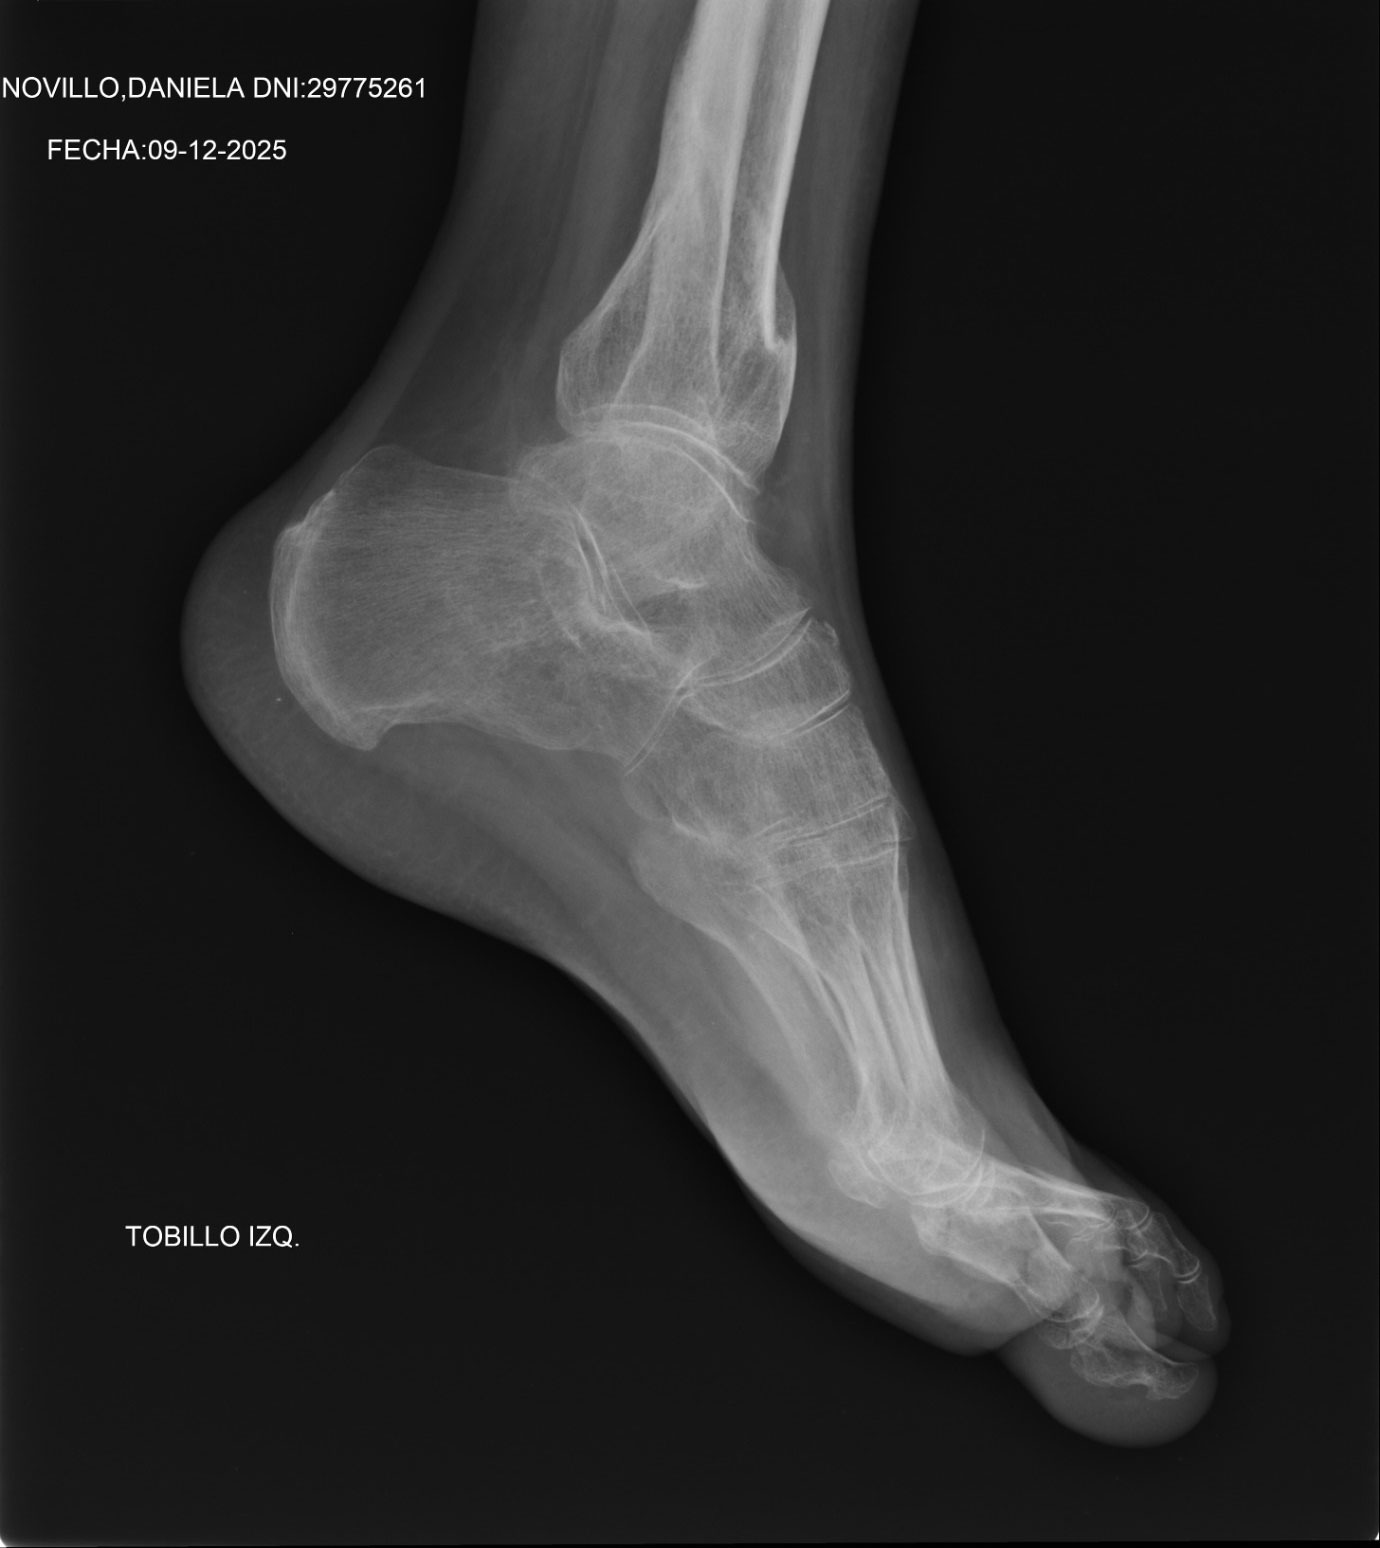

El 23 de junio del año pasado me tropecé y al caer me saqué el tobillo y me hice una pequeña fractura en la tibia. Me estuvieron viendo los médicos y primero me dijeron que me iban a operar, porque era operable y era la solución a la lesión que me había ocasionado.

Era un dolor fuertísimo, que no me dejaba caminar, no me dejaba dormir, los antibióticos que tomaba no me hacían efecto y ya no me hace nada efecto. Me hice ver con un médico en Azul, que es el que me está tratando en este momento, me hace una Tomografía completa y tengo el tobillo fuera de lugar, dos fracturas de tibia y el peroné abierto en 3 milímetros, a lo que me dejaron pasar sin operarme.